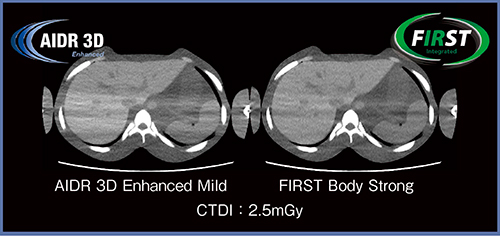

FIRSTは統計学的ノイズモデルを用いておりストリークアーチファクトの大幅な低減が可能であるが,それを実臨床で生かすための検討を行った。

腹部ファントムの両側に腕のファントムを置いた最もアーチファクトが発生しやすい状況で,撮影線量を0.6〜24.1mGyに変えながら撮影し,FBP(boost+),AIDR 3D Enhanced Mild,FIRST Standard,FIRST Strongを用いて再構成を行った。得られた画像のそれぞれ3か所にROIを設定し,各ROIのSDよりアーチファクトインデックス(AI)を算出して評価した。その結果,AIDR 3D EnhancedとFIRSTは,いずれもFBPよりAIが低く,低線量域ではFIRSTが最もAIが低かった。実際の低線量画像でも,FIRSTにて著明なアーチファクトの低減が確認できる(図4)。

図4 FIRSTによるアーチファクトの低減